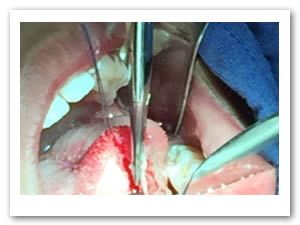

• Se colocó anestesia tópica y se infiltró localmente (lidocaína con epinefrina de 1: 100 000 al 2 %) a cada lado del frenillo lingual bloqueando nervio lingual bilateralmente. (Figuras 1 y 2).

Figura 1. Anestesia Local a cada lado del frenillo.

Figura 2. Anestesia Local del nervio lingual bilateralmente